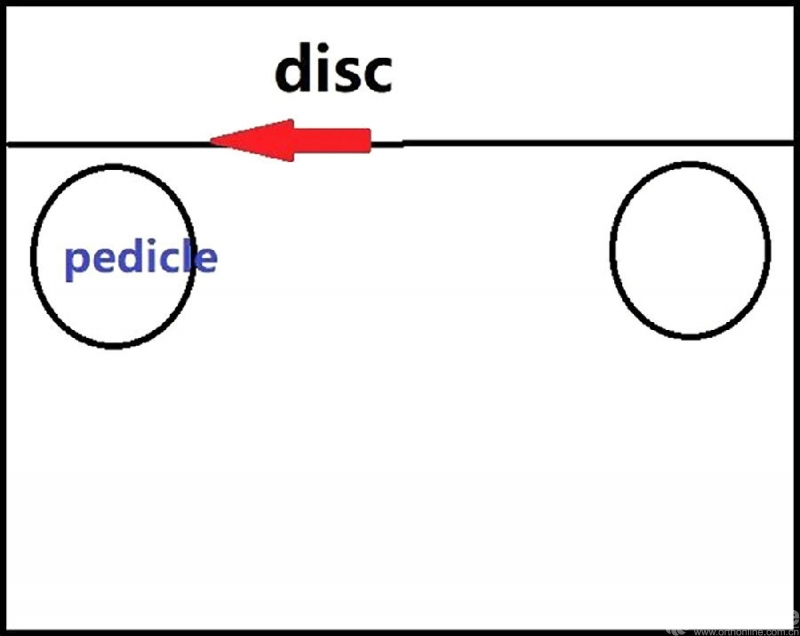

从标本上看,椎弓根其实就位于终板的下方,这是术中判断椎弓根位置的解剖标志。

与椎间盘的下缘平齐即是椎弓根的上缘。